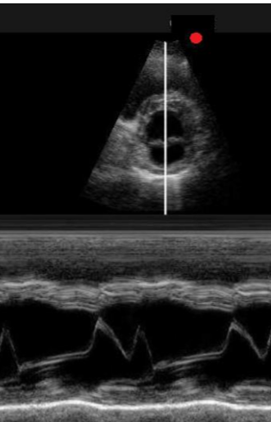

Describe M-mode for heart U/S.

A

Represents movement of structures over time.

Initially a B-mode image is acquired and a single scan line is placed along the area of interest.

M-mode shows how the structures intersected by the line move toward or away from the probe over time.

One dimensional image of structures.

Only structures associated with the cursor are seen. Depth on the Y axis, time on the X axis.

Records subtle change in wall and valve motion (chamber dimensions, fractional shortening, ejection fraction).

Used for accurate measurement of size.

M-mode in cardiac U/S